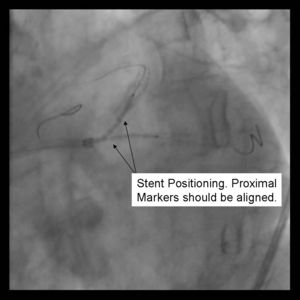

Benefits:

3) Both stents are advanced into the side branch and parent vessel. This may require further predilitation. Generally, the stents are advanced beyond the delivery point. Operator preference differs with respect to amount of overlap. Some operators form a long segment of overlap (>5mm), while others try to minimize overlap. It is absolutely essential that both vessels are covered during the balloon inflation. Optimal placement is ensured by advancing both stents distal to the intended deployment site then pulling them back into position. The proximal marker segements should be aligned, with positional confirmation in at least 2 separate views.